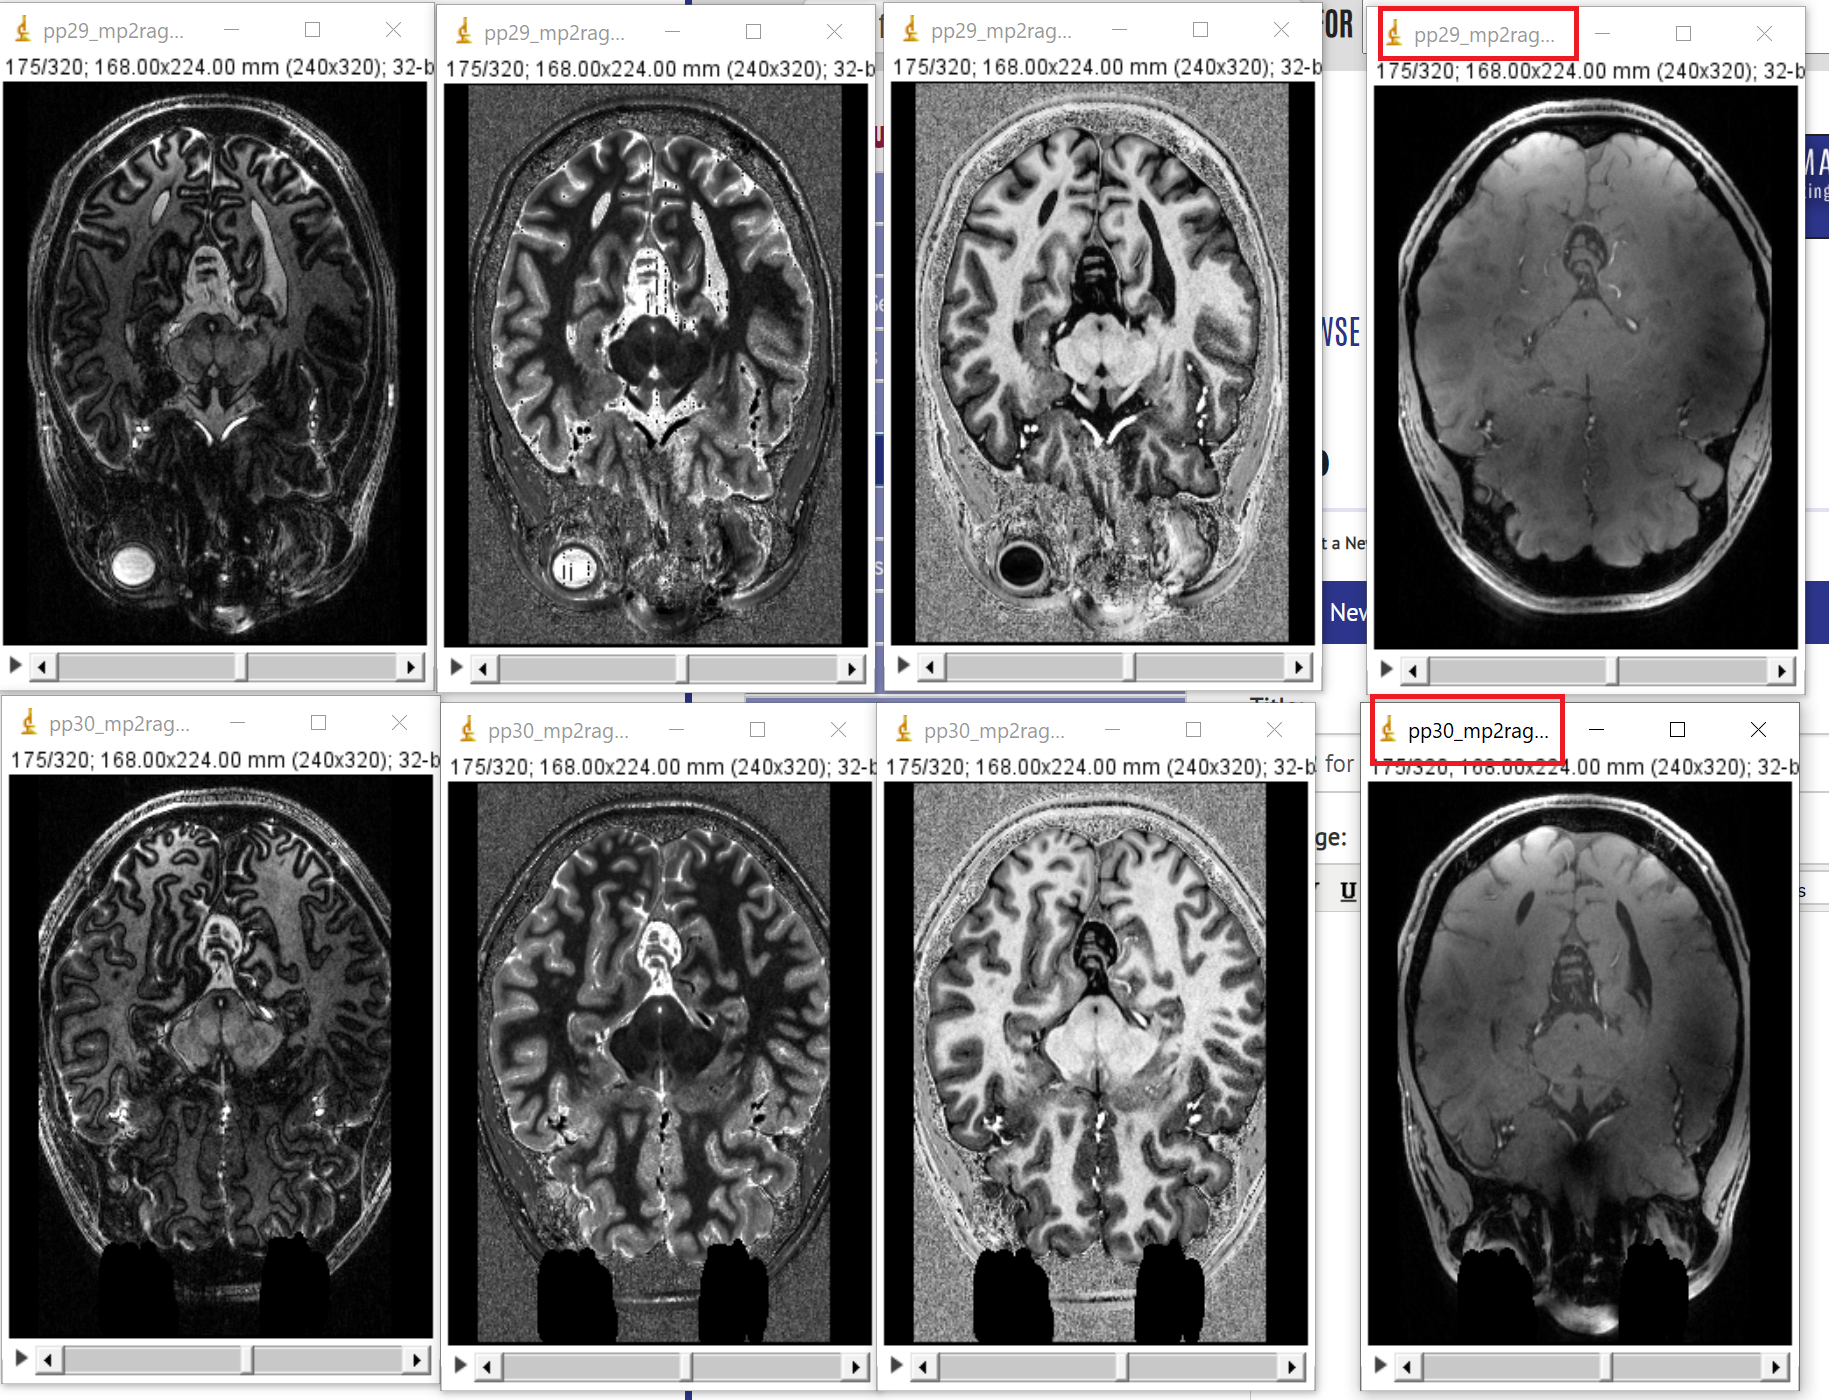

mp2rage_whole_brain_inv2 for pp29 and pp30 swapped?

is it just me or are the image for the whole brain inversion2 swapped for subject 29 and 30 (see attachment)? The other (uni, t1, inv1) seem to be right.